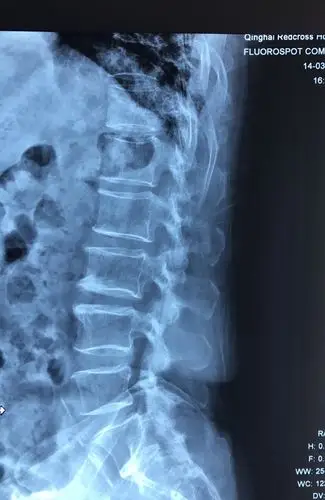

腰椎侧位

腰椎x线片,侧位片.

磁共振显示腰椎侧位l4/5椎间盘巨大型突出,l5/sⅠ椎间盘突出,脊髓